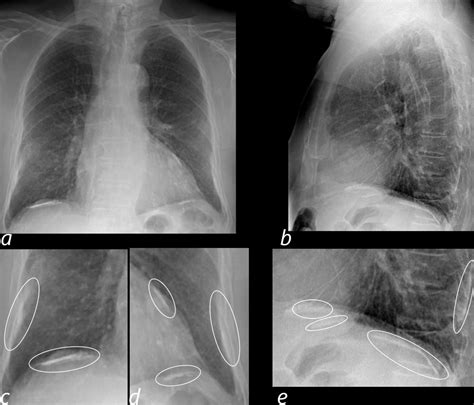

Diagnosing calcification in lungs involves a combination of medical history, physical examination, and diagnostic tests. Some of the common diagnostic methods include:

• Chest X-ray: A chest X-ray can reveal the presence of calcium deposits in the lungs.

• CT Scan: A computed tomography (CT) scan provides detailed images of the lungs and can help identify the location and extent of the calcification.